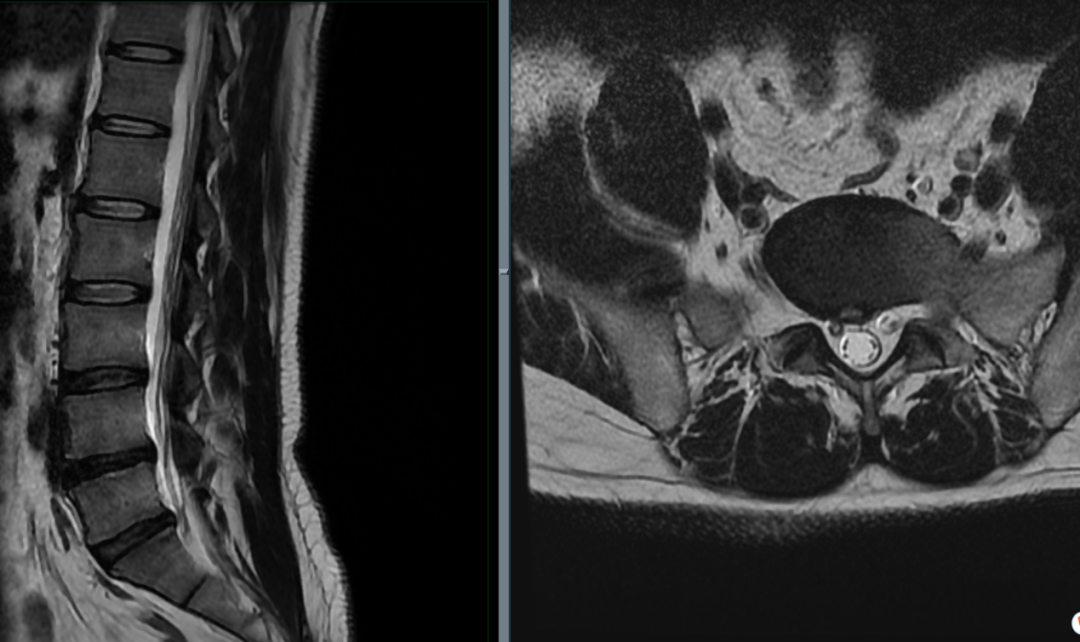

虽然我们说「 T1 序列看解剖,T2 序列看病变 」,但腰椎 MR 最重要的两个序列是 T2 序列矢状位 + T2 序列轴位(横断面)。矢状位序列帮助确定是哪个椎间盘,之后的评估将在轴位完成。

矢状面序列用以确定椎间盘位置

腰椎间盘轴位的解剖结构:腰椎间盘由三部分组成,中间是髓核,髓核之外包围着一圈纤维环,髓核上下各一软骨终板(也即正常椎间盘 = 上下软骨终板 + 纤维环 + 髓核)。

腰椎间盘 MR 评估需注意髓核、纤维环、后纵韧带等结构与神经根及硬膜囊的关系。

男性,35 岁,主诉腰椎酸痛伴右侧下肢麻痛 4 天来诊,否认外伤,完善腰椎 MR 检查图像如下:

L3/4 水平:

L4/5 水平:

L5/S1 水平: